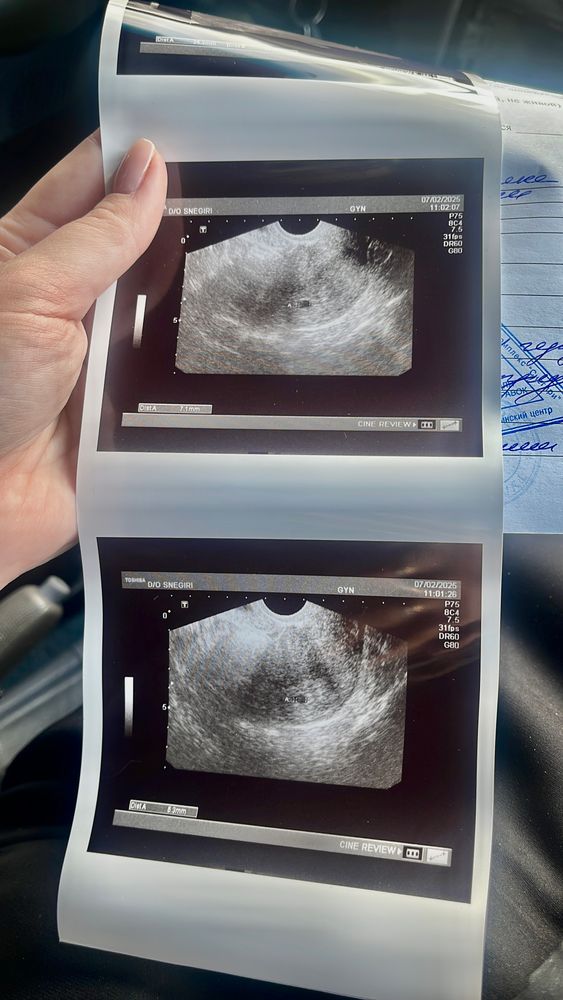

cherry, мес были 3.12 овуляция 12.01 тест начал полость 22.01

cherry, даа и хгч сдавала, судя по овуляции срок 5,5 акушерских

3,5 эмбриональных

У меня в 5 недель акушерских только пя было 3,4мм, сейчас на 6 неделе 11,9мм и жм 2,7мм, но по узи сказали 5 недель только, видимо из-за поздней О

У меня плодное яйцо 8 мм. Была на УЗИ на 5 нелеле ровно. Позвали на 7 неделе. Это вот в понедельник будет. Тогда и малыш будет и сердечко и мешочек. Не переживайте у некоторых на 5 неделе ПЯ меньше бывает даже.

Все отлично) У меня в 6 нед было только ПЯ 7 мм, через недельку уже ЖМ и эмбрион.

Рано пошли. Через неделю переделайте. У меня при пя 14, жм был 3

Желточный мешочек увидели в пя 12мм, второй пя был меньше- в нем не увидели. Через неделю в обоих были эмбриончики

На сроке 5.4 Пя было 5.5 мм, и больше ничего, через 2 недели уже эмбрион с сб